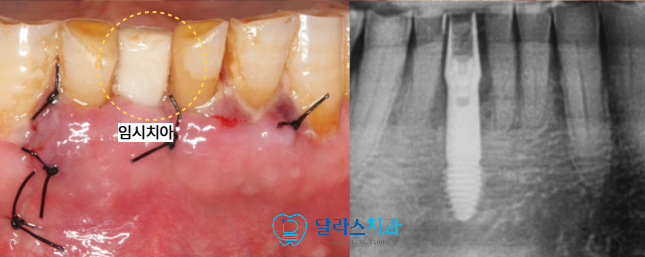

노원치과에서는 발치 치아 주변 치조골을 건들지 않도록

문제가 되는 치아만 정확하게 발치를 시행한 뒤

남아 있는 치조골을 면밀히 평가하여 즉시 임플란트를 식립하였습니다.

골폭이 제한적인 부위였기 때문에 정확한 위치 확보를 위해

세심하게 작은 지름부터 임플란트 크기에 맞는 지름까지 드릴링을 진행하였습니다.

부족한 부위는 골이식 재료로 보강하여 임플란트의 안정성을 높였습니다.

즉시 식립 후에는 잇몸 형태가 무너지지 않도록

임시치아를 바로 제작해서 부착해드림으로써 심미적인 회복도 함께 고려하였습니다.